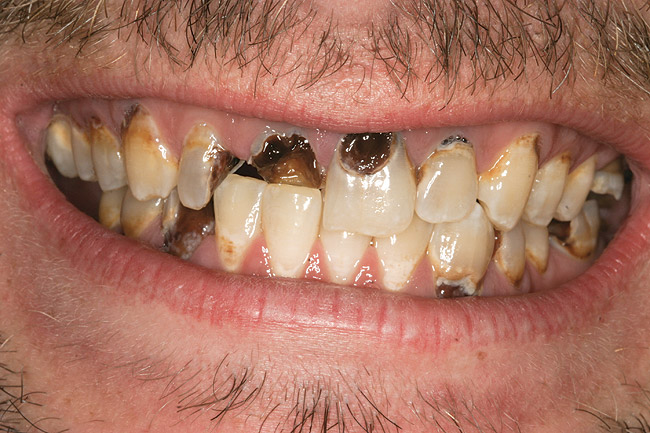

When smoked, methamphetamine produces highly toxic and corrosive fumes of lithium, muriatic, and sulfuric acids that can destroy enamel rapidly. With continued use, methamphetamine can produce severe, rampant caries, similar to early childhood caries. Patients have reported noticing changes in the appearance of tooth structure in as little as 3 months of use. The affected surfaces are the buccal and labial smooth surfaces, as well as the interproximal surfaces (Figure 1 through Figure 3). Because in the general population the vast majority of decay is found in the posterior molars, when someone presents with rampant anterior lesions it should be a red flag for methamphetamine use.5

Figure 1  DEVASTATING EFFECTS When smoked, methamphetamine produces highly toxic and corrosive fumes of lithium, muriatic, and sulfuric acids that can destroy enamel rapidly. With continued use, methamphetamine can produce severe, rampant caries. When someone presents with rampant anterior lesions it should be a red flag for methamphetamine use.

Figure 1